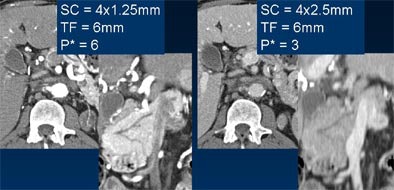

| Comparable image quality is seen in thick axial reconstructions of images acquired at 1.25-mm (upper left) and 2.5-mm collimation (upper right). However, coronal reformations of the pancreatic duct are markedly sharper from 4 x 1.25-mm data (lower left) compared with image acquired at 4 x 2.5 mm (lower right). SC = slice collimation, TF = table feed, P = pitch. Images courtesy of Dr. Mathias Prokop. |

The main thing to remember is to keep the slice width larger than the collimation, because if one acquires sections at 4 x 2.5 mm, for example, one cannot go back and reconstruct 1-mm thick sections. The reconstruction increment in MDCT works very similarly to that of single-slice CT: not much of an overlap is needed for viewing, but more slice overlap is necessary for MPR and 3-D imaging, Prokop said.